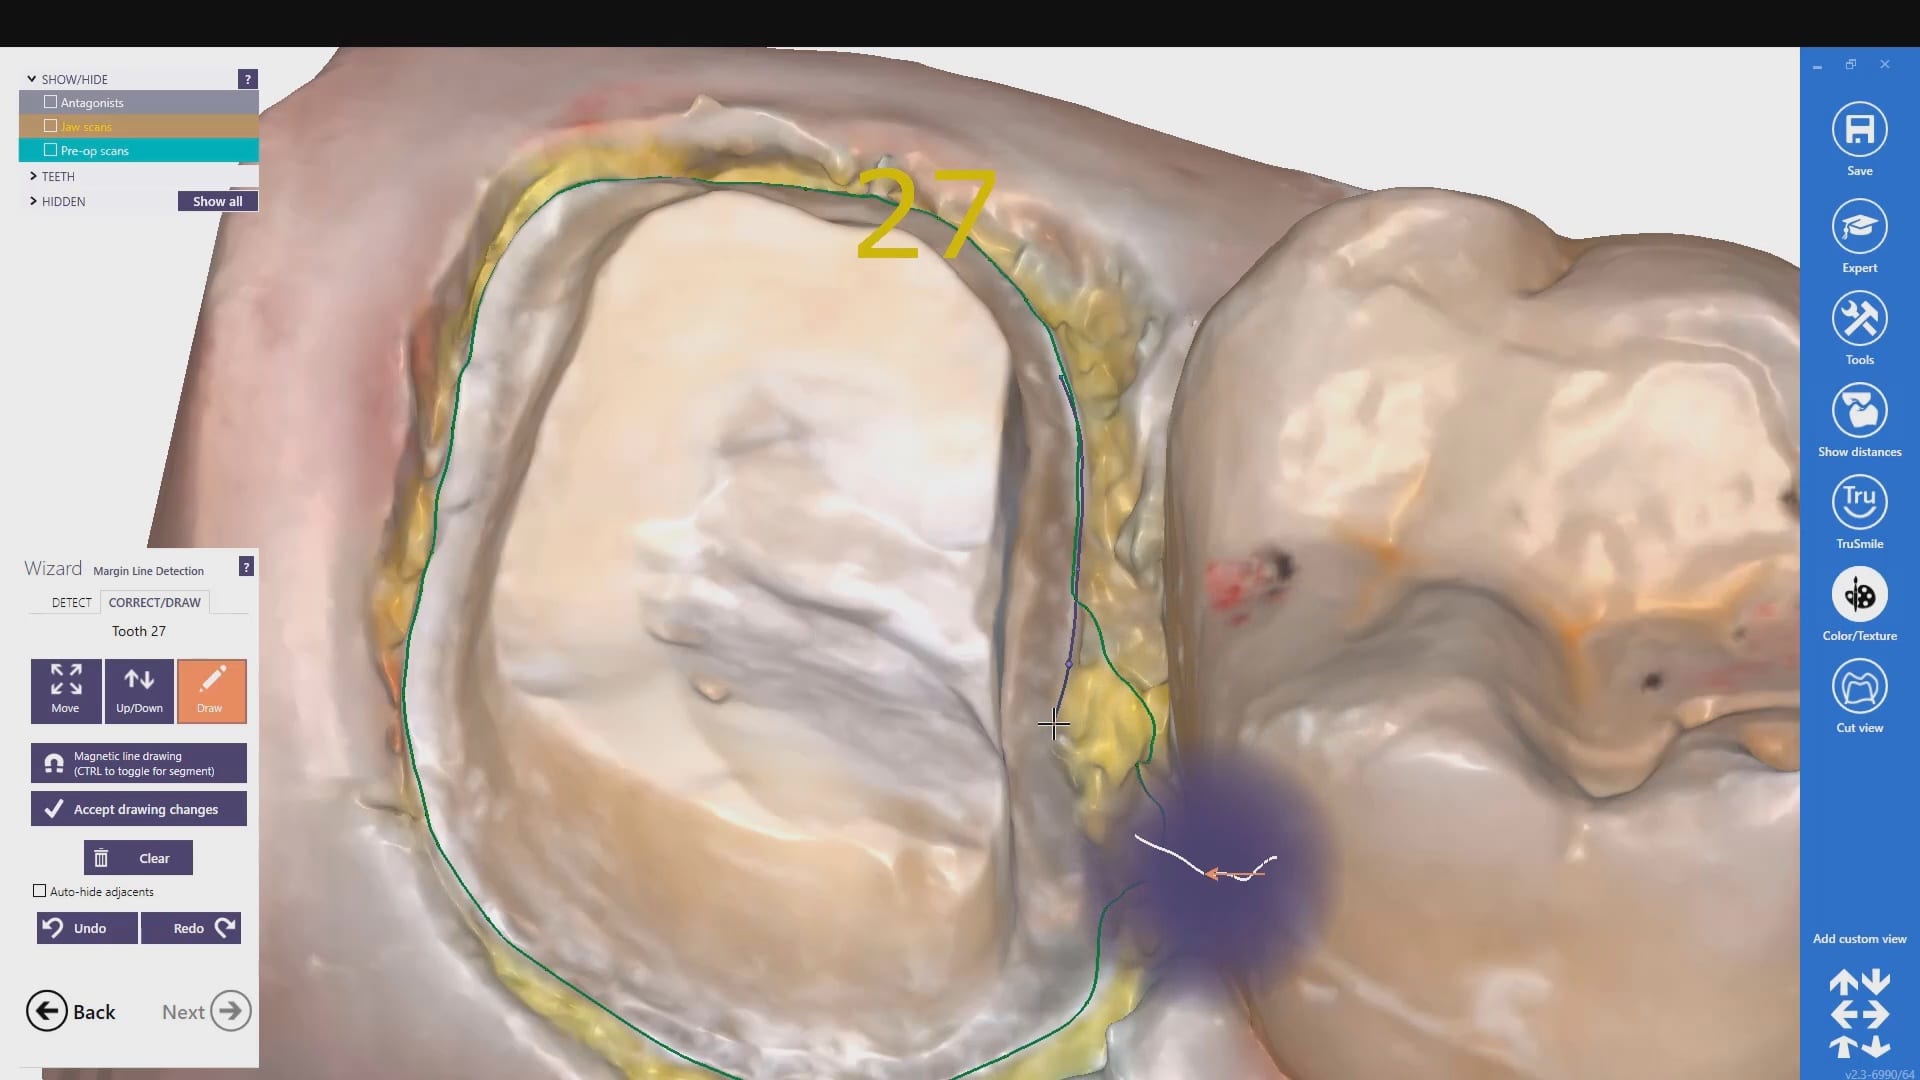

With analog dental impressions, it is imparative to separate the gum tissue from tooth structure and to create a trough for flash for dye work. This is not the case with the intra-oral scanner by Medit. All you need to do is displace the tissue so you have a clear line of site to the margins, and you just need to be flush. You don’t need flash like you do with stone work